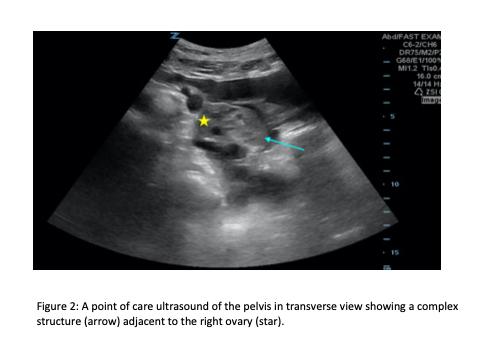

A 36-year-old female with a prior surgical history of hysterectomy without oophorectomy presented to the emergency department with lower abdominal pain. A POCUS revealed free fluid in the right upper quadrant with an unremarkable gallbladder. Subsequently, the pelvic POCUS noted free fluid as well as a heterogeneous structure in the right adnexa. The clinician ordered a serum beta human chorionic gonadotropin level, which was 173.2 international units per milliliter (lU/mL) (negative: < 5m IU/ml). Transvaginal ultrasound revealed a right adnexal echogenic structure with surrounding vascularity and moderate, complex free fluid suggestive of hemorrhage. Given the concern for possible ectopic pregnancy, obstetrics took the patient to the operating room where a right tubal ectopic pregnancy was confirmed.

一名36岁女性,既往有子宫切除术史,未行卵巢切除术,因下腹痛就诊于急诊科。POCUS显示右上腹有游离液体,胆囊无异常。随后,盆腔POCUS发现有游离液体以及右侧附件区有一个不均匀结构。临床医生检测了血清β-人绒毛膜促性腺激素水平,为173.2国际单位/毫升(IU/mL)(阴性:<5mIU/ml)。经阴道超声显示右侧附件区有一个回声结构,周围有血管,并有中度、复杂的游离液体,提示有出血。鉴于可能存在异位妊娠,产科医生将患者送往手术室,术中证实为右侧输卵管异位妊娠。